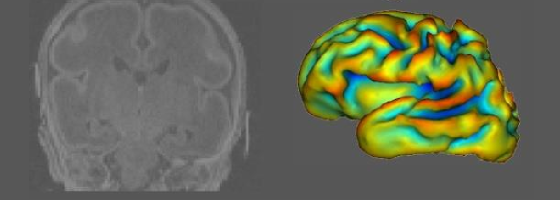

Bien plus que les enfants nés à terme, les enfants nés trop tôt risquent de développer des lésions cérébrales entraînant un retard neurodéveloppemental pouvant persister tout au long de leur existence. Une équipe de la Faculté de médecine de l’Université de Genève (UNIGE) et des Hôpitaux universitaires de Genève (HUG) spécialisée dans l’imagerie cérébrale des nourrissons a pu démontrer que l’administration, juste après leur naissance, de trois doses d’érythropoïétine, une hormone qui stimule la formation de globules rouges dans le sang, permet de réduire de manière importante les lésions cérébrales chez ces bébés. Des résultats à découvrir dans le Journal of American Medical Association (JAMA).